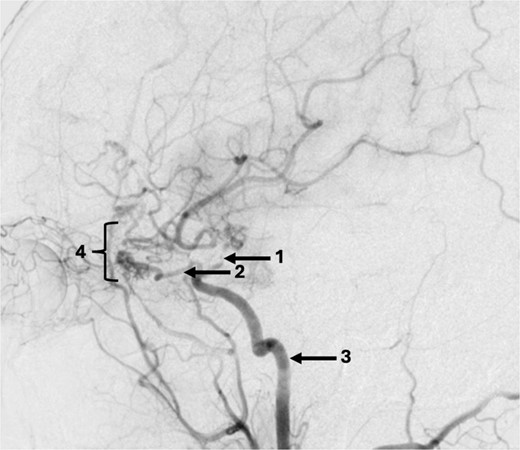

The DSA showed significant narrowing of the ACA and complete occlusion of the MCA distal to the clipped and fully occluded aneurysm. The right recurrent artery of Heubner, arising from A1, was hypertrophied and supplying the medial lenticulostriate territory. There was diffuse small vessel formation in this same area (Fig. 3). This DSA suggested the progressive distal stenosis secondary to the surgical clip led to anastomotic collateral formation, consistent with a radiological and clinical Moyamoya phenomenon. Patient’s symptoms were managed conservatively. Subsequent CT angiogram in 2018, 2021, and 2023 showed no further progression of the Moyamoya phenomenon.

Sagittal DSA demonstrating (1) Clip is in position across the terminal carotid. The frontal branch of the right MCA is supplied by collaterals from the (2) right ophthalmic artery (hypertrophied recurrent meningeal artery), right middle meningeal artery and right superficial temporal artery (via craniotomy site as pial synangiogenesis). There is collateral vessel formation consistent with Moyamoya phenomenon (4). (3) ICA. The A1 is not opacified likely due to the anterior communicating (ACOM) collateralisation.